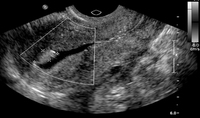

Normal hysterosalpingography (HSG)

From the collection of Dr Jared C. Robins